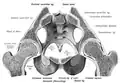

Полость таза и тазовые органы

Таз делят на два отдела: верхний, более широкий — большой таз (лат. pelvis major), и нижний, более узкий — малый таз (лат. pelvis minor), разделённые пограничной линией, проходящей через мыс крестца, дугообразные линии подвздошных костей, гребни лобковых костей и верхний край лобкового симфиза.

Полость большого таза является нижним отделом брюшной полости, здесь лежат органы нижнего отдела брюшной полости; малый таз скрывает мочевой пузырь, прямую кишку, а также у женщин — матку с её придатками и влагалище, у мужчин — предстательную железу и семенные пузырьки.

Основу таза образуют две тазовые кости, крестец и копчик, соединённые суставами пояса нижних конечностей в костное кольцо, внутри которого образуется полость, заключающая внутренние органы. До возраста 16—18 лет кости (подвздошная, лобковая и седалищная) соединены хрящами. Впоследствии происходит окостенение, и указанные кости срастаются между собой, образуя тазовую кость. Также при сращении этих костей образуется вертлужная впадина (лат. acetabulum).

Парные тазовые кости спереди соединяются при помощи лобкового симфиза, а сзади прикрепляются ушковидными поверхностями к одноимённым образованиям крестца, образуя парные крестцово-подвздошные суставы. Каждая из тазовых костей в свою очередь образована тремя составляющими: подвздошной костью, седалищной костью и лобковой костью, тела которых на наружной поверхности образуют вертлужную впадину (лат. acetabulum)— суставную ямку для головки бедренной кости, с которой образуют тазобедренный сустав.